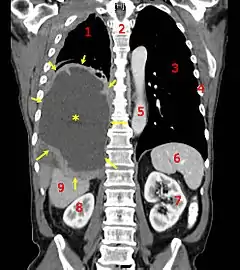

![]() A coronal CT scan showing a malignant mesothelioma, indicated by the asterisk and the arrows | |